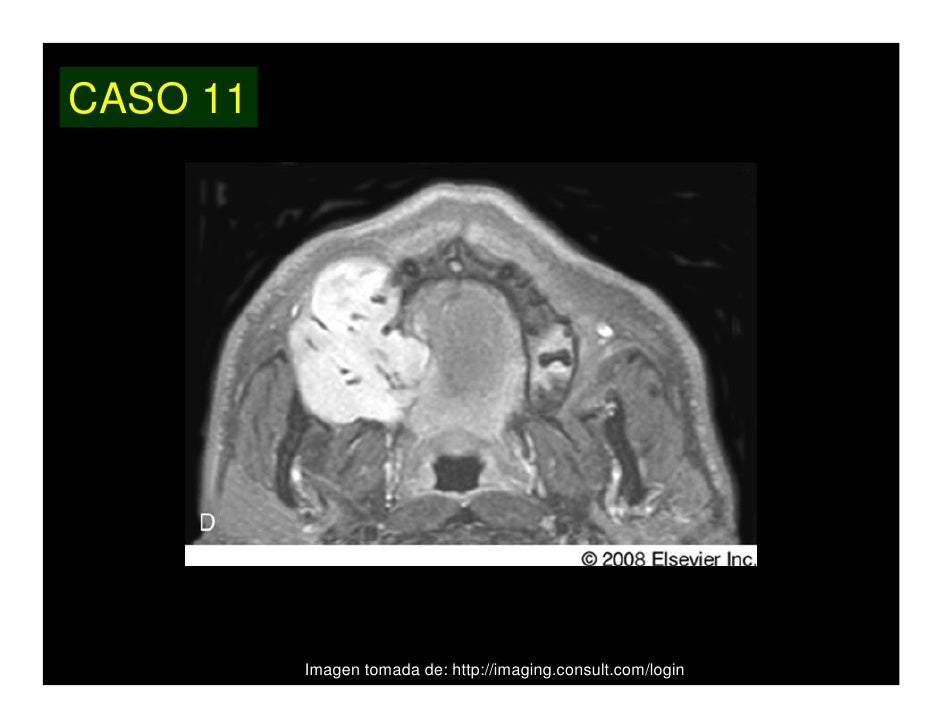

Debido a su agresividad local, se hace necesaria la resección quirúrgica con márgenes amplios. Se han descrito diversas técnicas quirúrgicas para la reconstrucción de defectos mandibulares segmentarios. El colgajo microvascularizado de peroné, en comparación con otros colgajos óseos, aporta la mayor longitud de hueso y, debido a la naturaleza de su aporte vascular, confiere una completa libertad en la selección del lugar de osteotomía, con la posibilidad de recrear un arco mandibular preciso, tras la resección ósea. Se utiliza la técnica de preformado in situ del peroné, mediante la cual se replica el contorno mandibular por medio de osteotomías mientras el pedículo vascular del injerto sigue unido a la pierna. Se consigue, de este modo, disminuir substancialmente el tiempo de isquemia del colgajo. La realización de la técnica en "doble barra" y la colocación posterior de implantes osteointegrados constituye un método óptimo en la reconstrucción de pacientes dentados sin atrofia maxilar.